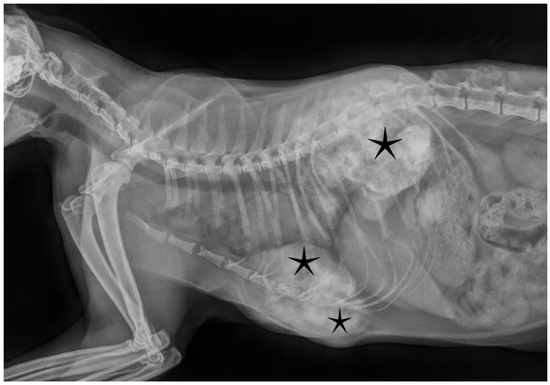

2. Case Presentation

2.2. Results